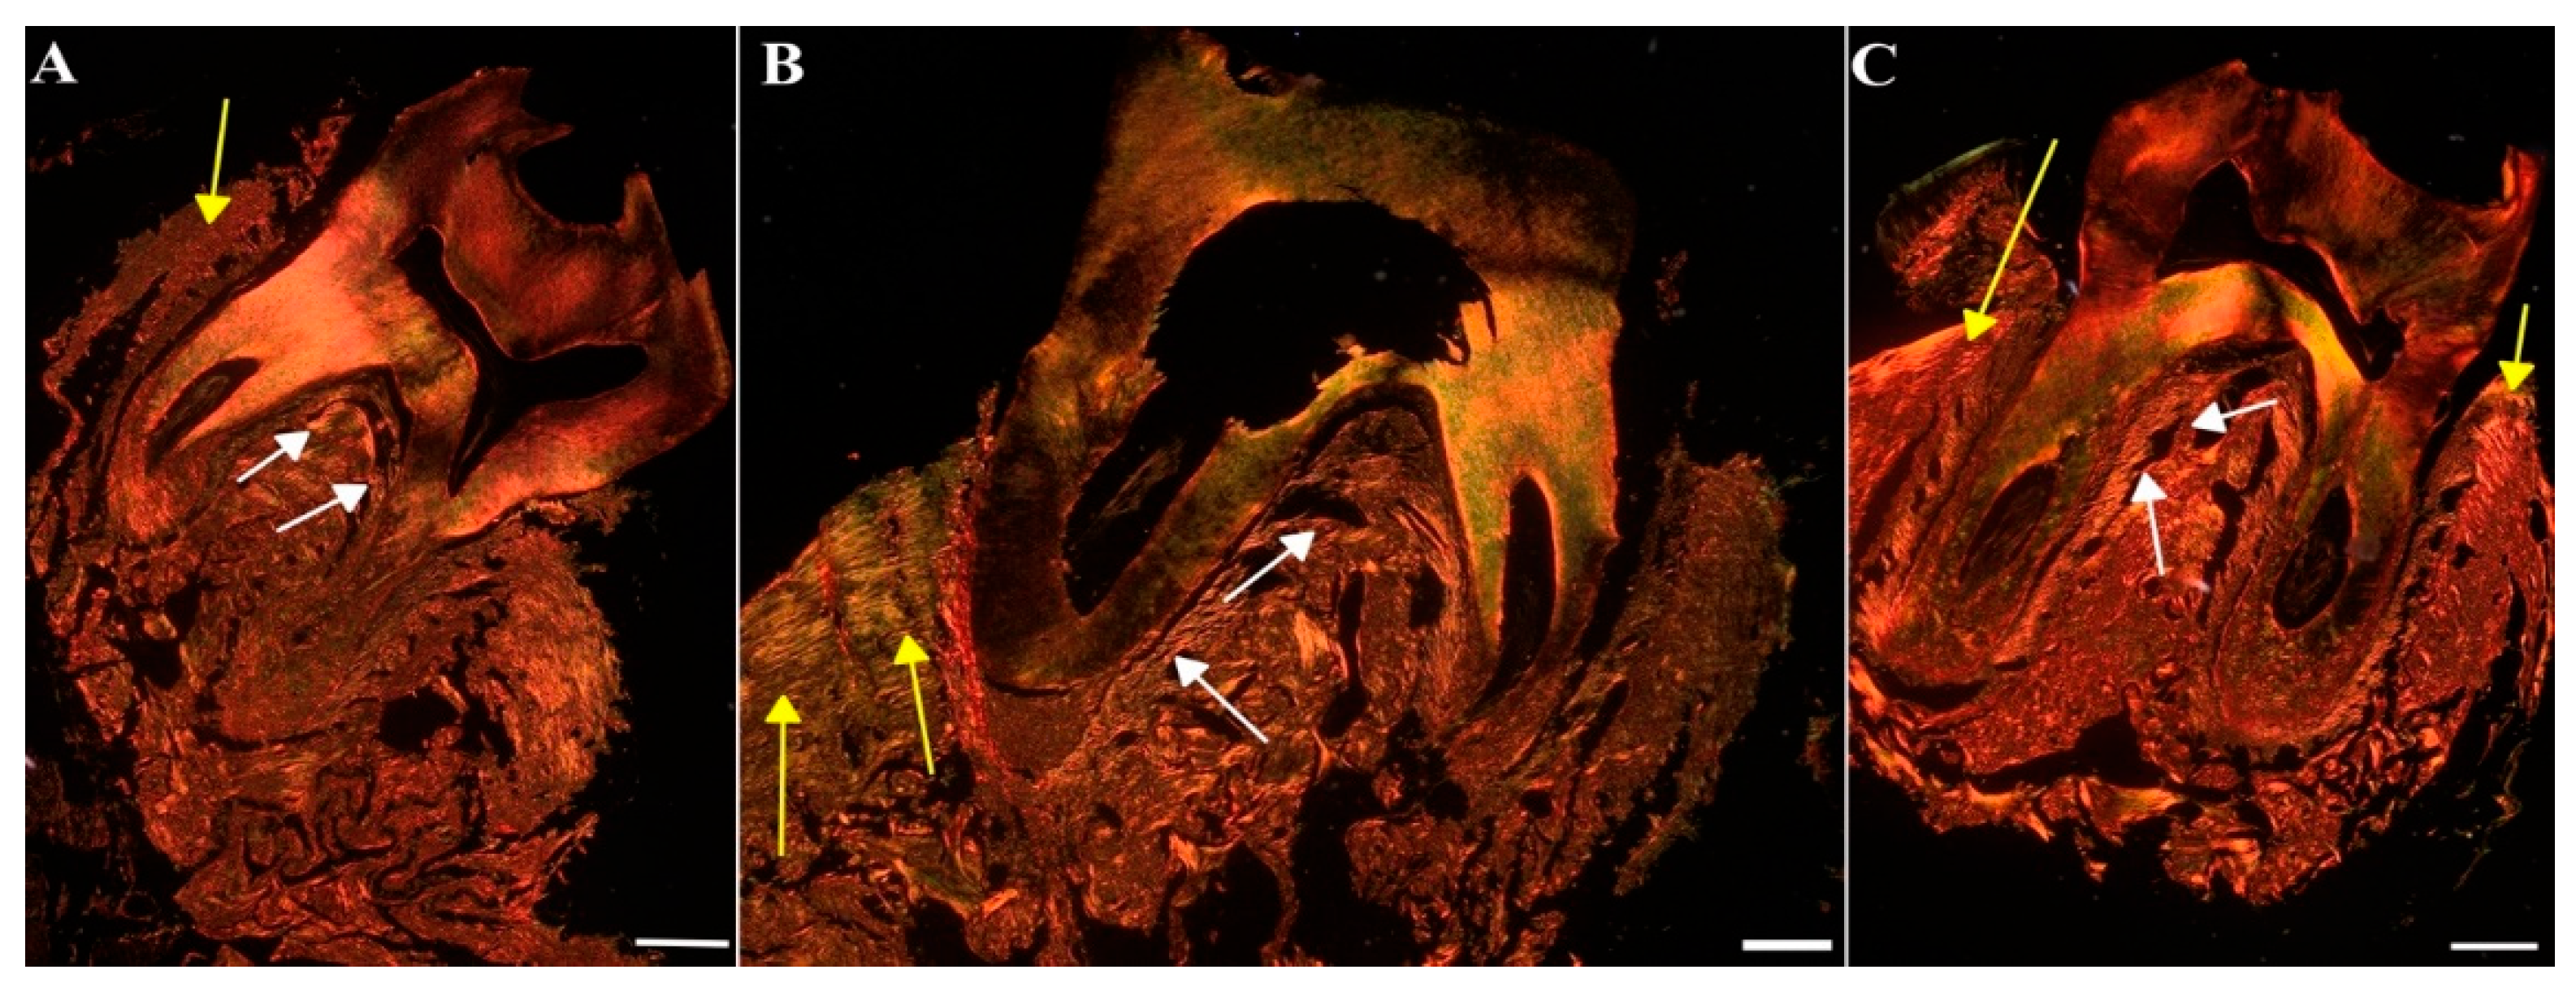

To assess the impact of MIN-T on the bone structure changes during periodontitis, immunohistochemical analysis of rat jawbone was conducted. Picrosirius red (PSR) staining was used to distinguish young and maturated collagen fibres in both compact and trabecular bone (indicated by yellow and white arrows, respectively, in Figure 11).

Significant differences (p < 0.05) were observed between the groups (Table S2): control (CG), untreated periodontitis (PG), and periodontitis pretreated with MIN-T (PG+MIN-T). Post-treatment, the trabecular bone volume (BV/TV) was slightly reduced in the treated group (PG+MIN-T), while it remained similar in both the control (CG) and untreated periodontitis (PG) groups. Additionally, there was a significant (Table S2) increase in trabecular separation in the maxillary bone of the treated group (PG+MIN-T) compared to the control (CG) and untreated (PG) groups. This increase may indicate a potential weakening of the trabecular bone's microarchitecture in the individuals who received the drug.

Other parameters, such as trabecular number (Tb.N) and trabecular thickness (Tb.Th), showed no treatment effects on the microarchitecture of the trabecular bone (Table S2). For the trabecular bone, coarse collagen bundles were more prevalent in both the control group (CG) and the treated group (PG+MIN-T) compared to the infected, untreated group (PG) (Table S3), where bone tissue structure appeared significantly weakened.

The ratio of fine-fibrous young to coarse-fibrous maturated collagen (Y/Mcompact) in the maxillary compact bone was significantly (p < 0.05) lower in the treatment group (PG+MIN-T) than in both the control (CG) and untreated (PG) groups (Table S3). This suggests that the local administration of the minocycline formulation may have induced the synthesis of new collagen. Furthermore, the proportion of maturated coarse-fibrous collagen (%Mcompact) in the compact bone of the maxilla was higher in both the treated (PG+MIN-T) and untreated (PG) groups compared to the control group (CG) (Table S3), indicating a compromised bone structure in the area due to the infection with P. gingivalis.

Interestingly, in the PG+MIN-T group, the size of the intertrabecular spaces) in the maxillary bone was significantly larger compared to the control (CG) and non-treated (PG) groups, suggesting a potential weakening of the trabecular bone microarchitecture. Additionally, the non-treated periodontitis group PG exhibited a decrease in the percentage of maturated coarse-fibrous collagen and a significant increase in the percentage of fine-fibrous collagen, and the ratio of young fine-fibrous to maturated coarse-fibrous collagen ) bundles within the trabecular bone of the maxilla compared to both control and treated animals PG+MIN-T. This might indicate disturbances in the collagen network of the trabecular bone in the jaws of infected rats, suggesting that drug administration positively affects bone turnover by eradicating the bacteria, and indicating induction of new collagen synthesis following an anti-infective treatment.

Moreover, the percentage of coarse-fibrous collagen (%Mcompact) in the compact bone of the maxilla was significantly increased in both untreated (PG) and treated (PG+MIN-T) animals compared to controls (CG), signaling a compromised bone structure in this area of the maxilla due to an infection with P. gingivalis. In summary, while the administration of MIN-T does not enhance the microarchitecture of the trabecular bone in the maxilla, it also does not significantly deteriorate it. Furthermore, drug administration does not significantly impact collagen synthesis, which could potentially increase the stability of collagen fibres and improve the condition of the trabecular bone.

Histomorphometric analysis of the jawbone

Maxillary bones from every animal were isolated, soft tissue was removed and decalcification in an Osteomall commercial decalcifier (Sigma-Aldrich, St. Louis, MO, USA) was performed. Decalcified samples were dehydrated in graded ethanol solutions and embedded in paraffin. From each rat, coronal (frontal) sections (5 µm thickness) from the molar region were cut with a microtome. For the trabecular bone, Toluidine blue staining was performed. To differentiate collagen type in trabecular- and compact bone picrosirius red (PSR) staining was employed. The sections were analyzed with an Olympus CX43 microscope (Olympus, Tokyo, Japan) equipped with filters providing circularly polarized illumination. Objective magnification of 4x and 10x was used to collect images. The bone microarchitecture was assessed using ImageJ software (NIH, Bethesda, MD, USA). The following parameters were determined: bone volume (BV/TV), mean trabecular thickness (Tb.Th mean), maximal trabecular thickness (Tb.Th max), mean trabecular space (Tb.Sp mean), maximal trabecular space (Tb.Sp max), and trabecular number (Tb.N) as well as the distribution of thin (immature) collagen fibres, the distribution of thick (mature) collagen fibres and the proportion of the mature and immature collagen fibres in the trabecular- and the compact bone. The analysis was done about all molars, corresponding values are presented in Tables S2 and S3.

Figure 11. Representative images of the jawbone of Wistar rats: Sirius red staining in picric acid used for the determination of different collagen types. [A] Control group (CG), [B] periodontitis group (PG), [C]: periodontitis + MIN-T group (PG+MIN-T). Scale = 200 µm. Yellow arrows mark compact bone, white arrows mark trabecular bone.